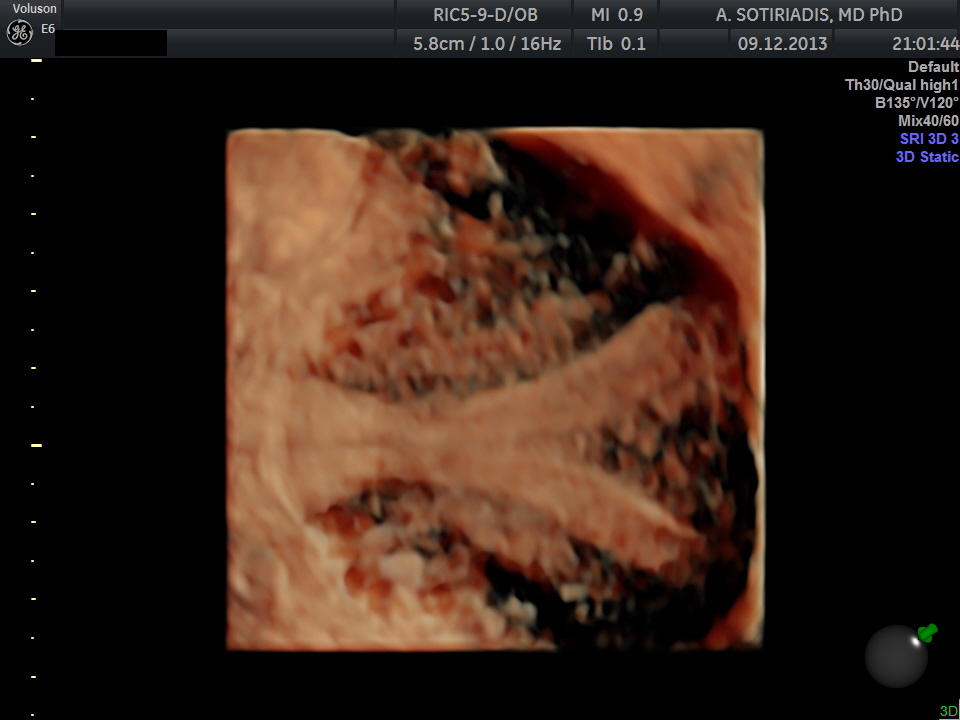

The patient was scanned on a GE E6 Voluson Expert machine (GE Healthcare, Milwaukee, WI), using a RIC5-9-D vaginal 4D probe. The uterus was originally scanned in a longitudinal plane and a 3D volume was taken. The reconstruction of the uterus on the coronal plane was done using the OmniView / Polyline modality and render modality with GYNSurfaceHD surface setting.

Three-dimensional reconstruction showed a midline septum running throughout the uterine cavity and the cervix, with normal contour of the uterine fundus. Therefore the diagnosis of a complete uterine septum as per the American Fertility Society, or a Class U2bC1 anomaly (complete uterine septum with septate cervix) as per the European Society of Human Reproduction and Embryology / European Society of Gynecologic Endoscopy (ESHRE/ESGE) new guidelines (3) was made (Figures 1 and 2).

Figure 2: Reconstruction as before using the render modality with GYNSurfaceHD surface setting.